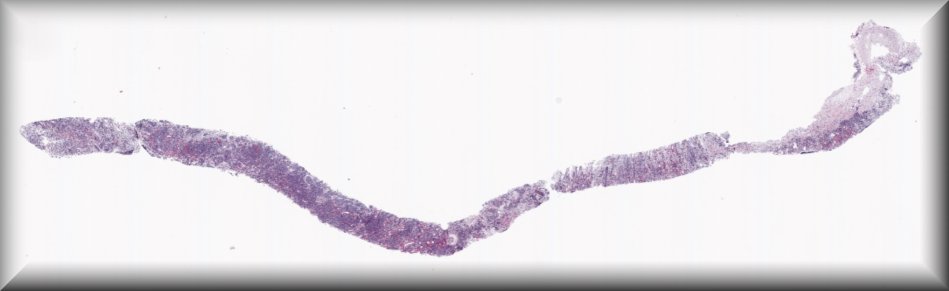

Preparacion virtual

Visor HTML5

Visor NZH

Diagnóstico